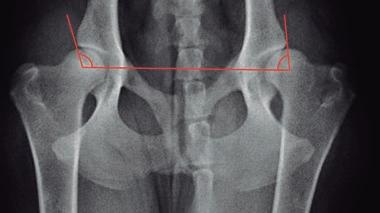

Displasia de cadera (I): etiopatogenia, signos clínicos y pruebas diagnósticas 26